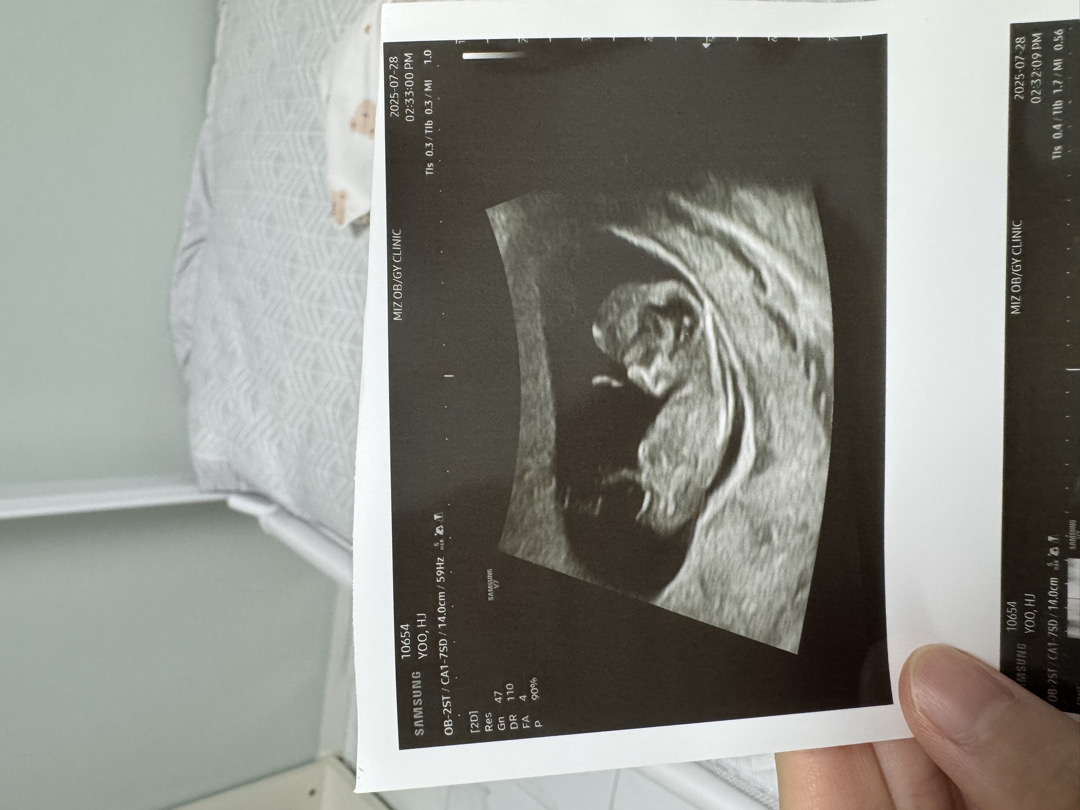

10주 4일 각도법 참견 부탁드려요 🫶🏻

아들 딸 각도법 참견 부탁드려요